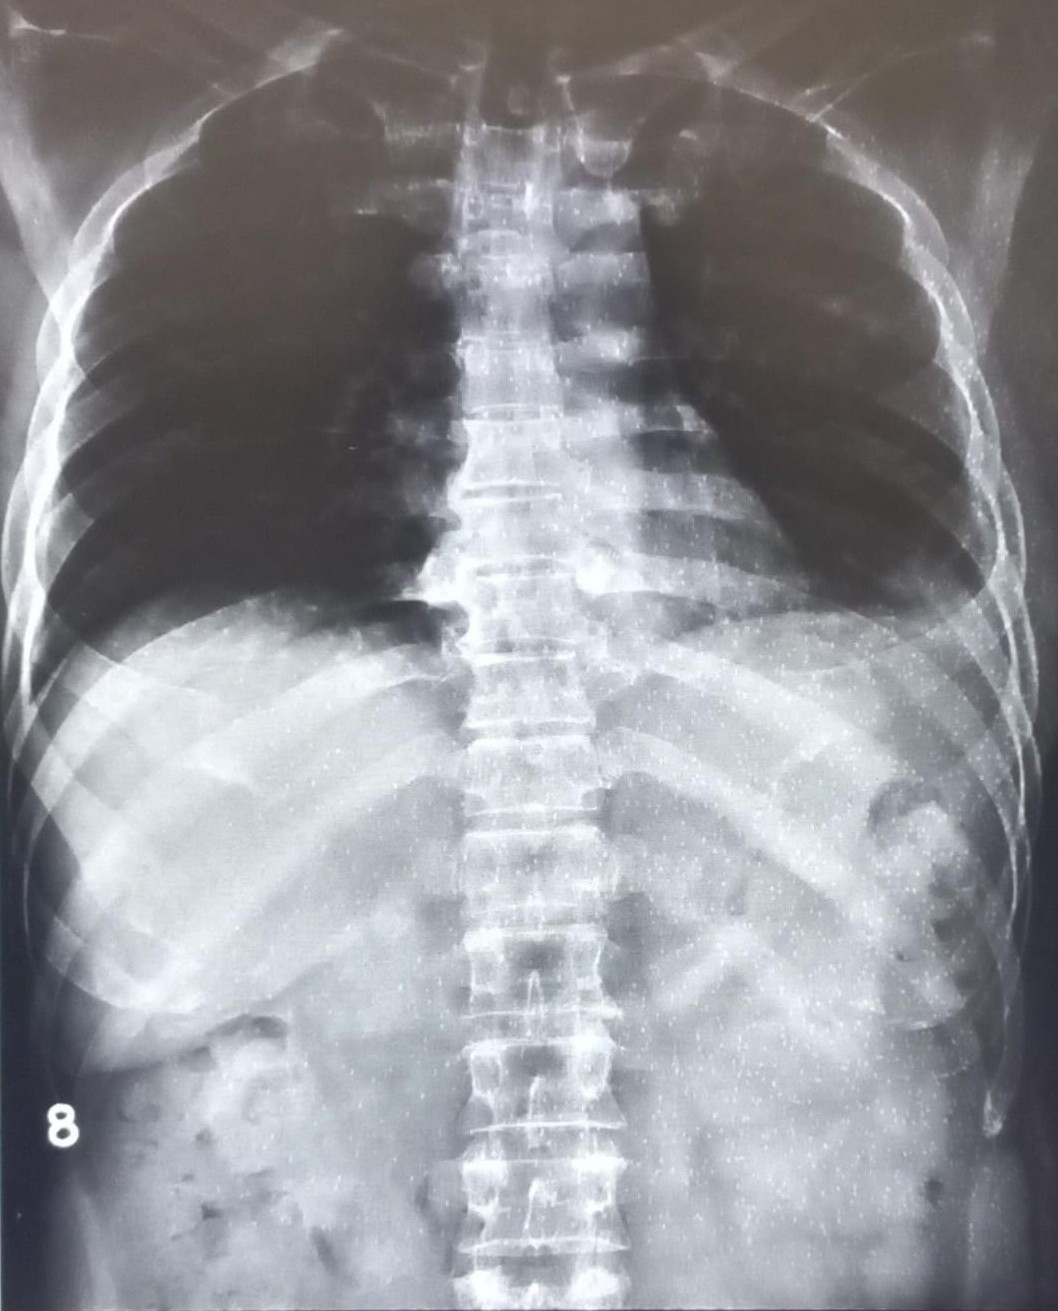

| 4437 | IGGMC, Nagpur, Nagpur | P2 | 29-35 | narendra parate | Consent taken on Paper | 25 Yrs. |

Provisional Diag : Cronic Cough

Final Diag : pleural effusion |

TB Case (Confirmed) | right CP angle blunted, suggestive of right sided pleural effusion | Abnormality visible on x-ray |